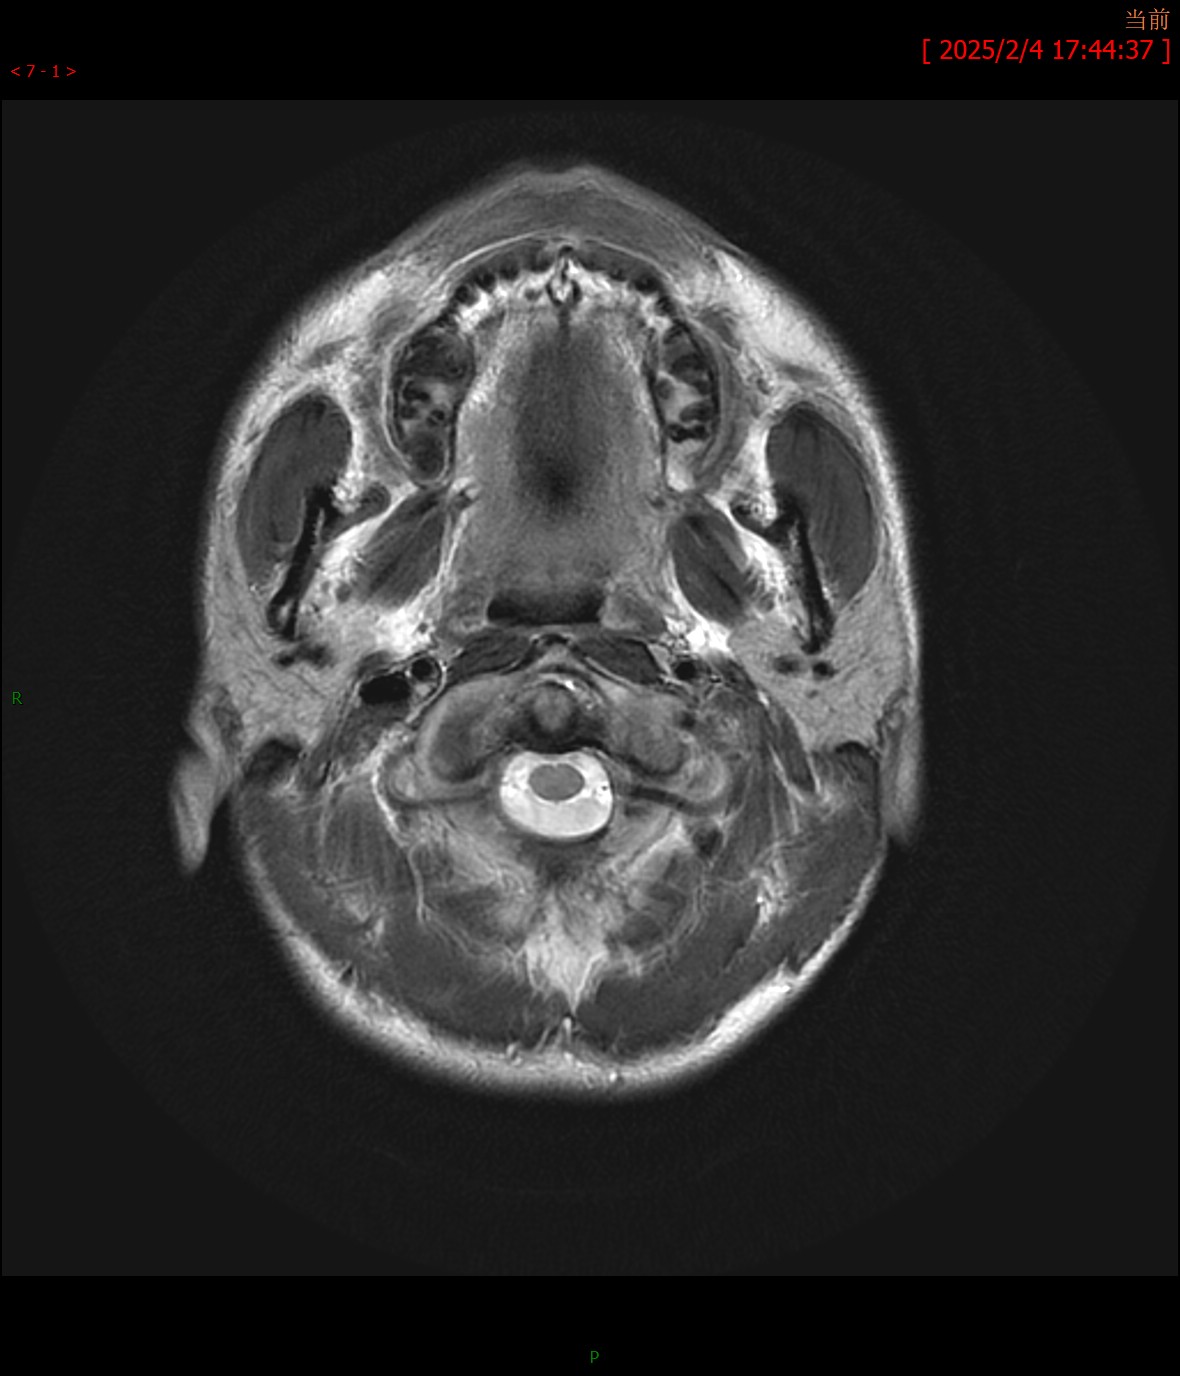

T1WI矢状位 T2WI横轴位

MRA颅脑MR平扫:双侧桥臂、右侧小脑半球、延髓、桥脑、中脑、双侧豆状核、壳核可见多发斑片状稍长T1、T2信号,边界不清,病灶于T2FLAIR呈高信号,大致呈对称性分布。脑室系统轻度扩大,脑沟、脑裂增宽,中脑、小脑体积缩小,中线结构未见移位。

影像学诊断:1. 双侧桥臂、右侧小脑半球、脑干及基底核团多发异常信号伴脑萎缩改变,符合肝豆状核变性颅脑表现;2. 颅脑MRA未见明显异常。

最常见的影像表现为T2WI和T2-FLAIR图像上双侧壳核(70%)、尾状核(60%)、丘脑腹外侧(55%~60%)和中脑(50%)出现对称性高信号,这些区域反映了该病铜沉积的选择易损性特征;有时也可见脑桥(20%)、延髓(10%~15%)和小脑(10%)高信号,大脑白质(25%)和小脑白质(10%)可见局灶性或弥漫性融合状高信号。其机理主要是铜沉积于脑组织中,造成反应性水肿、神经元及胶质细胞缺失、海绵样变性和胶质增生,进而引起不可逆性的空腔和囊变。在未经治疗或治疗效果不佳时,随病程的延长,铜沉积逐渐增多,由于铜顺磁性作用,最终可形成T2WI低信号。T1WI图像上病变信号强度多样,部分病例的受累区表现为低信号,而部分病例则表现为高信号,类似慢性肝性脑病,反映了铜的顺磁性效应。对称性基底节异常信号同时伴有脑干病灶是该病的影像特征。当病变发展到一定程度时,随着神经元及胶质细胞广泛坏死、变性,常出现基底核团及脑干萎缩表现,甚至可出现全脑萎缩。

“熊猫脸征”常见于Wilson病,分为“大熊猫脸征”和“小熊猫脸征”,是该病在脑干结构选择易损性的影像学表现。T2WI图像上“大熊猫脸征”出现在中脑层面,红核为对称性低信号,构成熊猫的眼睛,而红核以外的中脑顶盖结构高信号构成熊猫的上半身白色轮廓,侧面的黑质网状部的正常信号构成耳朵,上丘低信号构成嘴巴。“小熊猫脸征”出现在脑桥被盖层面,内侧纵束和中央被盖束呈低信号构成小熊猫眼睛,导水管开口进入第四脑室的高信号构成鼻子和嘴。需要注意的是“熊猫脸征”并非Wilson病脑部MRI特征性表现,其他疾病如Leigh病、脑干梗死、EB病毒相关性脑炎、甲硝唑脑病、甲醇中毒及缺血缺氧性脑病等也可出现该征象。